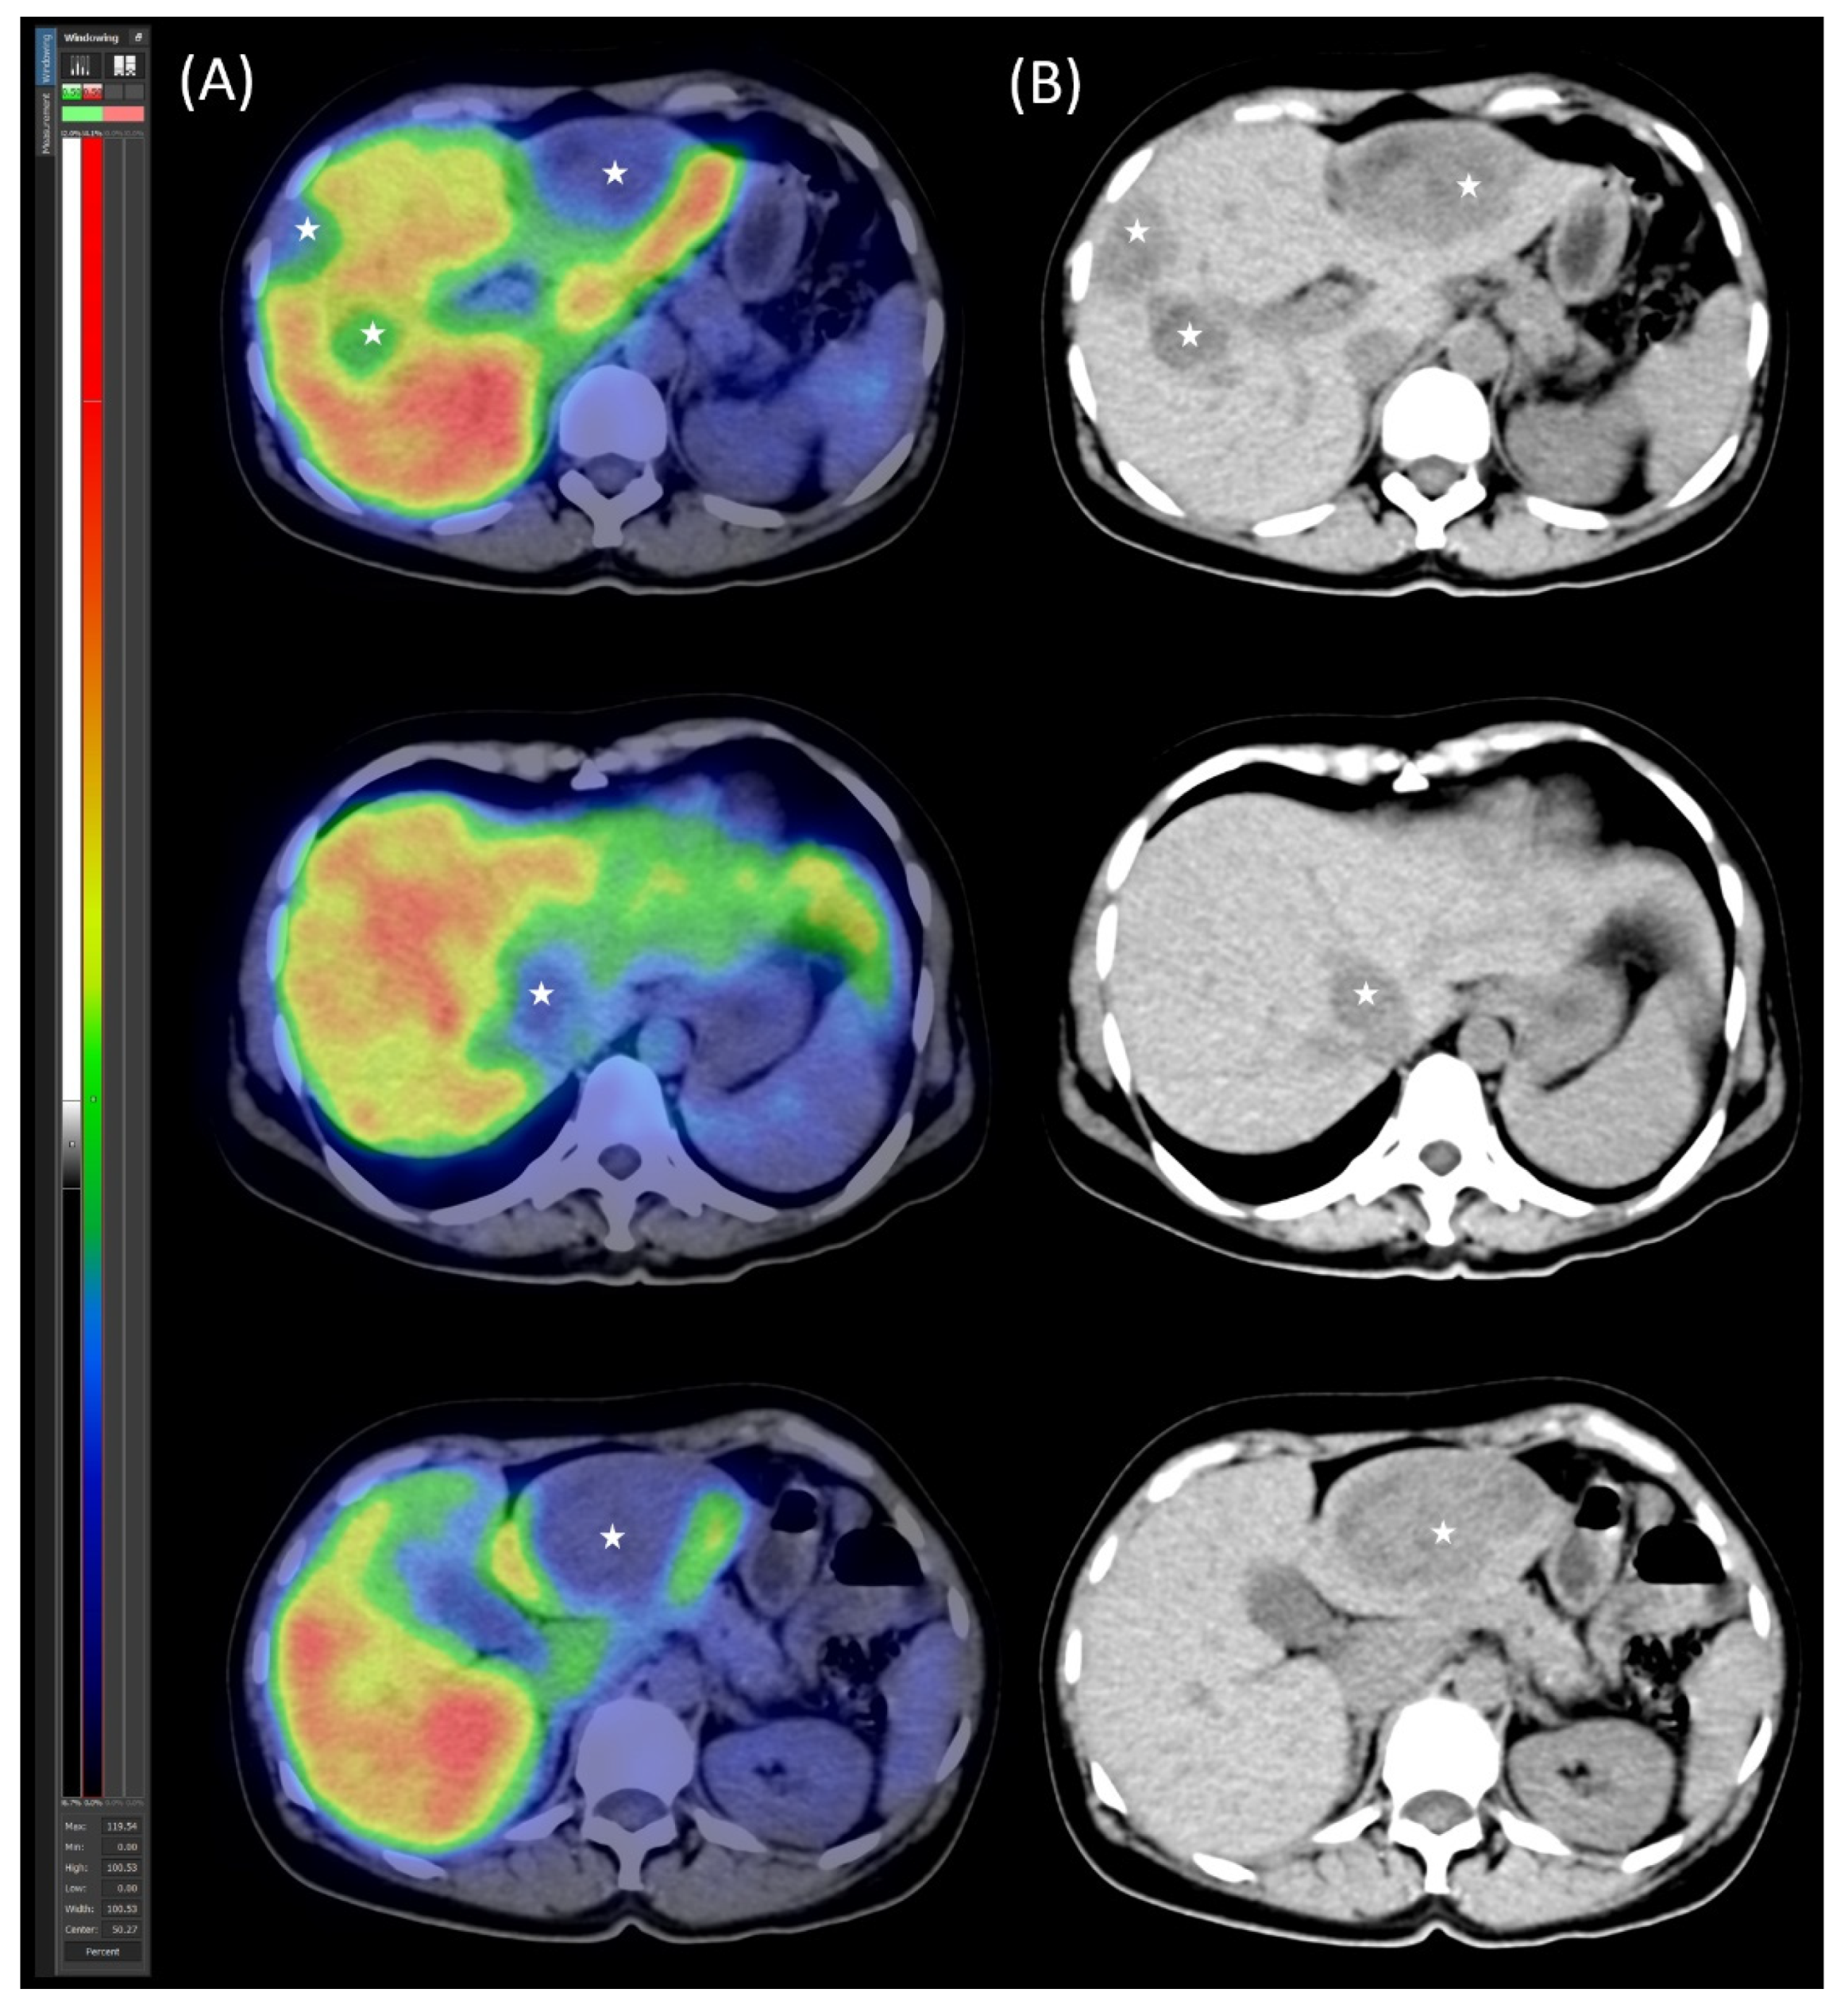

2.2. Preoperative Planning and First-Stage Surgery